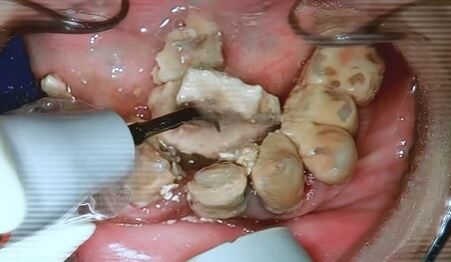

圖片來源:Dr. Eric Chan陳澔賢醫生

不過更多人關心的是後續治療問題,有位網友提出關鍵疑問:「牙結石清除後牙齒還能保留嗎?還是得全部拔掉再植牙?」陳醫師專業解釋,像這種嚴重狀況基本上需要進行「全口拔除」處理,但也不能立刻拔牙,必須先進行洗牙、等待數天後再做處理,「不然可以想像有多少細菌會經由傷口跑進去體內」,顯見口腔衛生的重要性真的不容小覷。